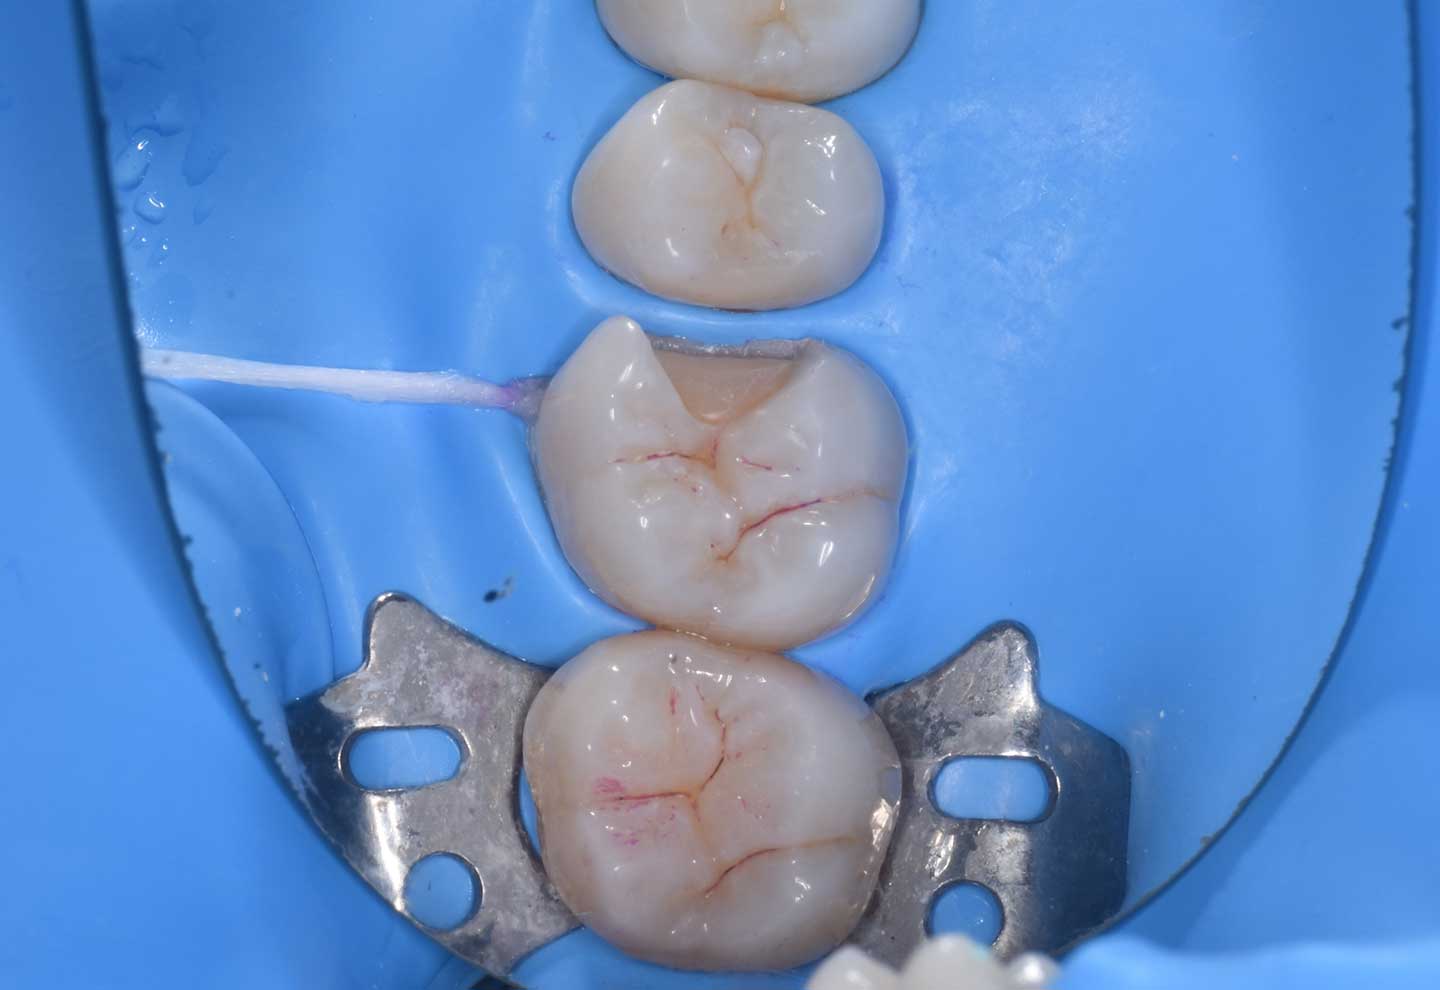

ラバーダムとは何ですか?

-

セラミックを長持ちさせるための、防湿処置です。 歯は、唾液や湿気がある状態では 接着が弱くなります。 ラバーダムは 治療する歯だけを隔離し、 完全に乾いた状態を作るためのシートです。 見えない工程ですが、 この処置の有無で 接着精度と寿命は大きく変わります。 当院では ラバーダム、IDS、精密接着など 長期安定を前提とした工程を 徹底しています。

例えば、湿度が高いお風呂場、サウナ

ラバーダムの有無は治療の予後、長持ちするかしないかに大きく差が出ます。

私自身、口腔内にセラミックが入っているのですが、ラバーダムをしない環境でセラミックをつけるというのは絶対嫌だったので、ラバーダムをつけてからセラミックをセットしてくれる先生にお願いしてつけてもらった経験もあります。